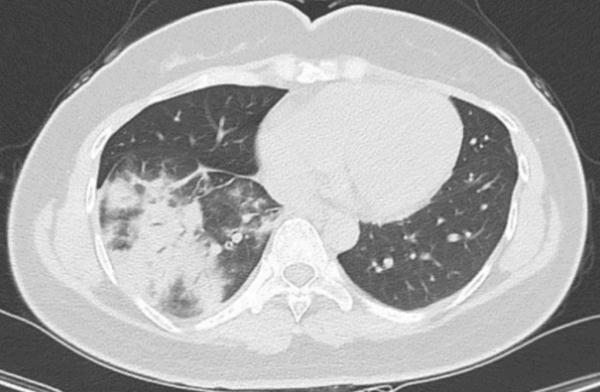

于是,朱女士来到省二医呼吸与危重症医学科门诊寻求治疗。何耀为医师通过胸部CT检查,发现她的右肺下叶有感染性病变,于是将其收治住院,进一步完善检查。

治疗前胸部CT片显示右肺下叶可见多发小片状、斑片状密度增高影

医生通过支气管镜检查,发现朱女士的右下肺支气管有大量黄白色黏痰,通过快速病原学检测发现了“肺炎支原体”。也就是说,朱女士不仅感染了肺炎支原体,病情还比较严重,被确诊为肺炎支原体肺炎。